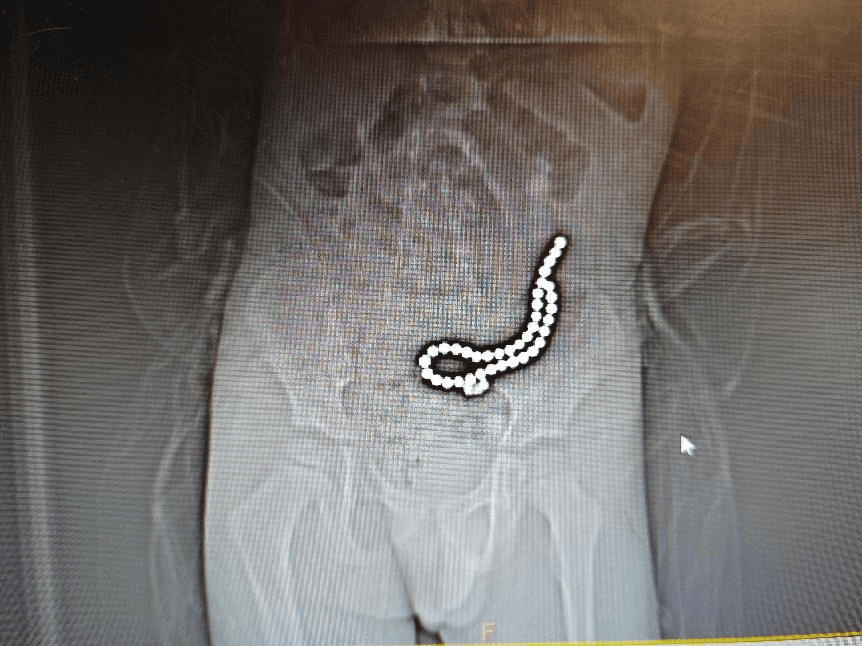

磁力珠色彩绚丽、玩法多样,深受小朋友喜爱。但如果误食,后果却会很严重。 近日,丽江市人民医院接收了一名因误吞磁力珠而生命垂危的小儿患者。这名4岁的孩子,在家中玩耍时,不慎吞下了多达37颗磁力珠。这些磁